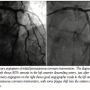

Case report. A 63-year-old male patient suffered from non-ST-segment elevation myocardial infarction (N-STEMI). He had no other past medical history. He was treated initially medically with aspirin, clopidogrel, enoxaparin, bisoprolol, perindopril, and rosuvastatin. Peak level of CK-MB was 139.1 ug/L. Four days later, diagnostic coronary angiography was performed. Significant stenoses were seen in the ramus circumflex (RCx): a 40% stenosis of the ostium of the RCx and a proximal RCx lesion of 70% in a large posterolateral (PL) branch. We also saw 80% stenosis in the left anterior descending artery (LAD) just after the first diagonal branch (D1). The patient was referred to our center for an elective PCI of the lesions in the LAD and PL branch.

First, the lesion in the LAD was treated. Two guidewires were placed, 1 in the LAD and 1 in the D1 for protection because of its large size. This side branch was not involved (ie, Medina 0.1.0); a 3.0 mm x 18 mm Blazer (Orbus Neich) BMS was placed in the LAD across the D1 (provisional single stent strategy). A minor plaque shift was observed, but flow in the D1 was not compromised (TIMI 3 flow). Therefore, no additional side branch treatment was performed (Figure 2). In addition, the PL branch was treated with good result.